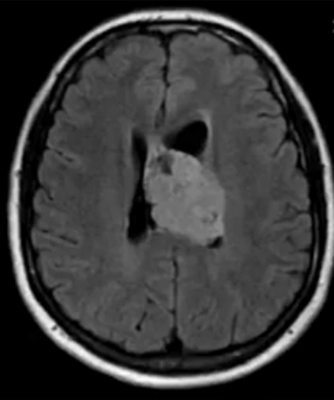

Метастазы в головном мозге на постконтрастном изображении (указаны стрелками)

Множественные метастазы в вещество головного мозга на МРТ без контраста

- метастазы. Выглядят, как множественные образования в тканях головного мозга различных размеров, неправильной формы, с неровными контурами, накапливающие контраст, с различной интенсивностью отека вокруг;